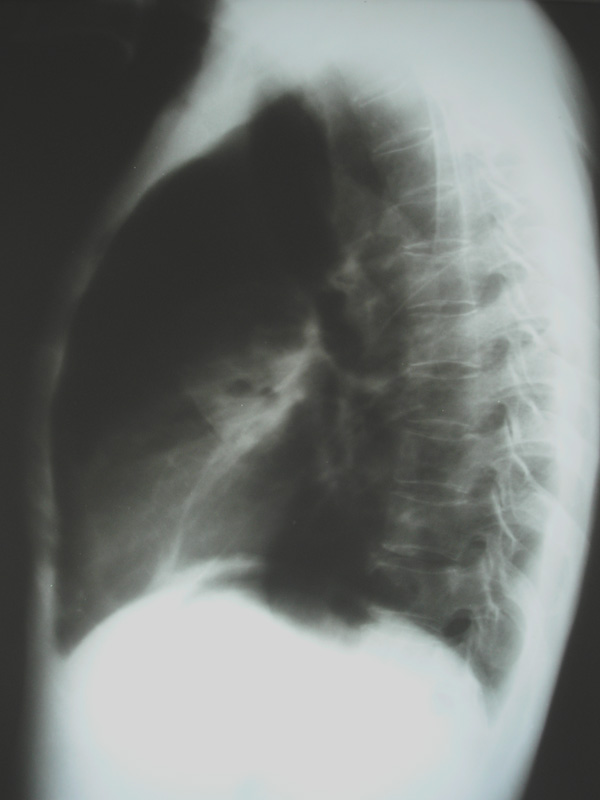

男,42岁,发烧、咳嗽、身体消瘦月余.

侧位可见后壁偏心空洞,有液气平面,tb?肺ca?